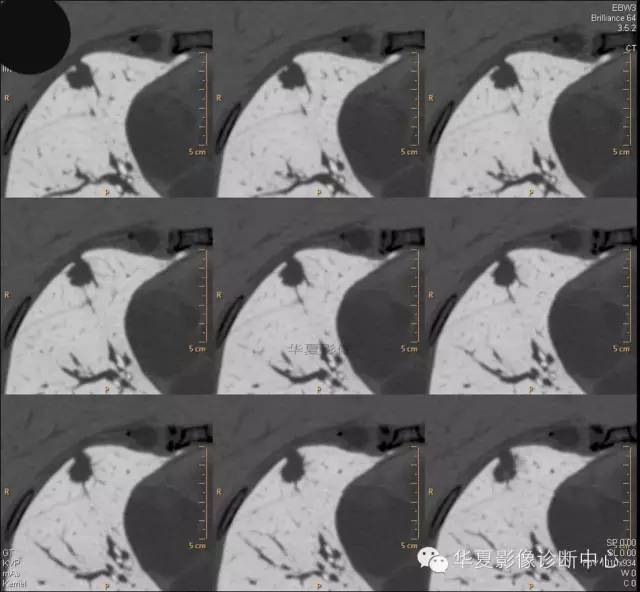

女,56岁,其父因肺癌去世,自觉胸部疼痛不适来诊要求拍胸片。

检查所见: